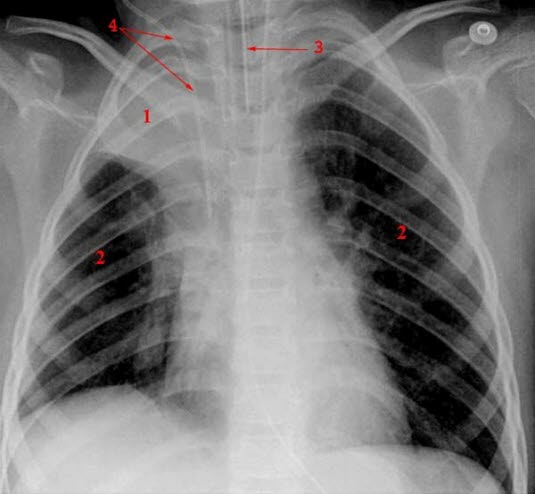

1. Atelektase av hele høyre overlapp

2. Normalt lungevev

3. Trakealtube

4. CVK (sentralt venekateter)